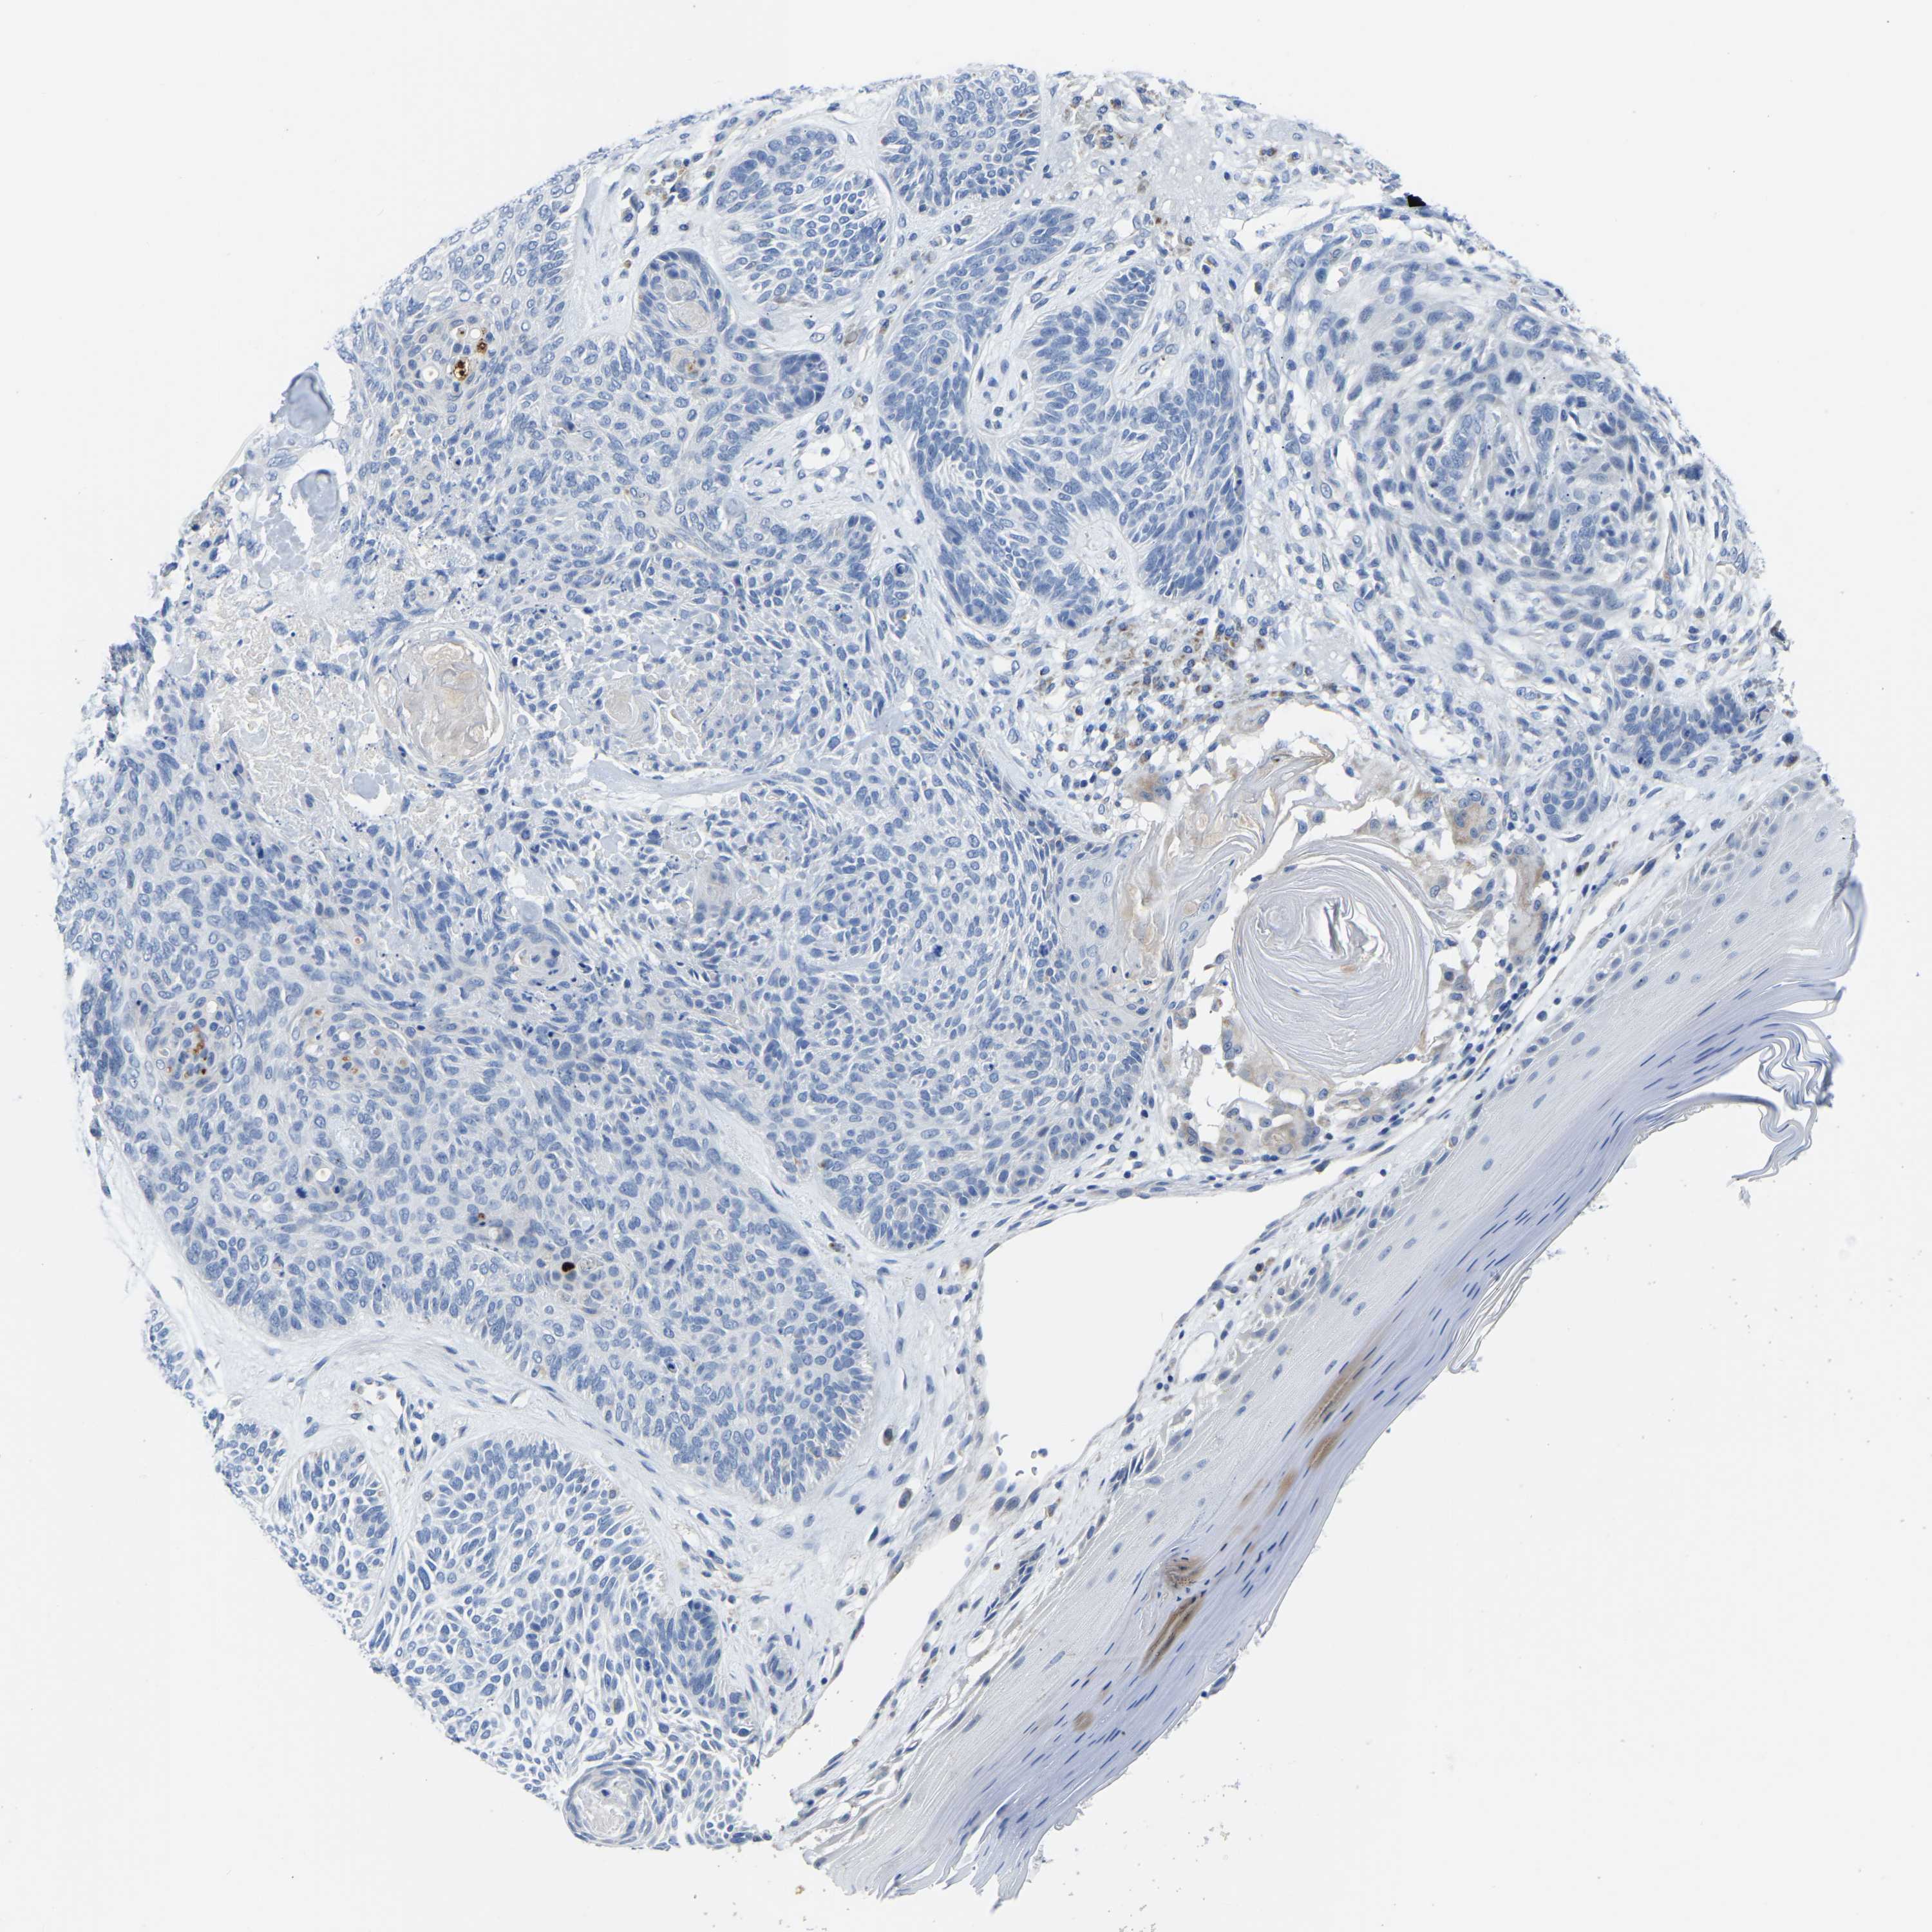

SKIN CANCER - Protein expressioni

A mouse-over function shows sample information and annotation data. Click on an image to view it in a full screen mode. Samples can be filtered based on level of antibody staining by selecting one or several of the following categories: high, medium, low and not detected. The assay and annotation is described here.

Each image is clickable and will lead to virtual microscopy that enables deeper exploration of all samples and also displays staining intensity scores, fraction scores and subcellular localization as well as patient and tissue information for each sample.

Antibody HPA018990

Staining

Not detected

Negative

None

Basal cell carcinoma